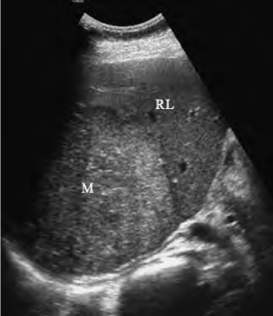

9.超声造影检查 原发性肝癌大多数在造影动脉相整体增强呈高回声,门脉相呈等回声或低回声,延迟相为低回声,表现为“快进快出”型(图23-18)。

图23-18 原发性肝癌超声造影

A图为超声造影动脉相,肿瘤整体增强呈高回声(↓)所示,B图

为延迟相呈低回声(↓)所示,表现为“快进快出”型